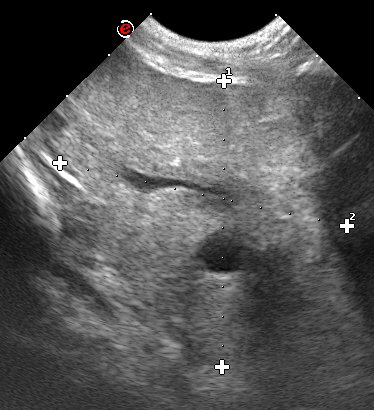

Diseases of the prostate are very common in older dogs that have not been castrated and can be life threatening. More and more dogs in Australia are being left entire so these diseases will increase in prevalence. Familiarity with these diseases can be lacking.

We have much experience in treating these diseases through experience in working in Europe. We can diagnosis prostatic diseases accurately and treat the most common ones medically.